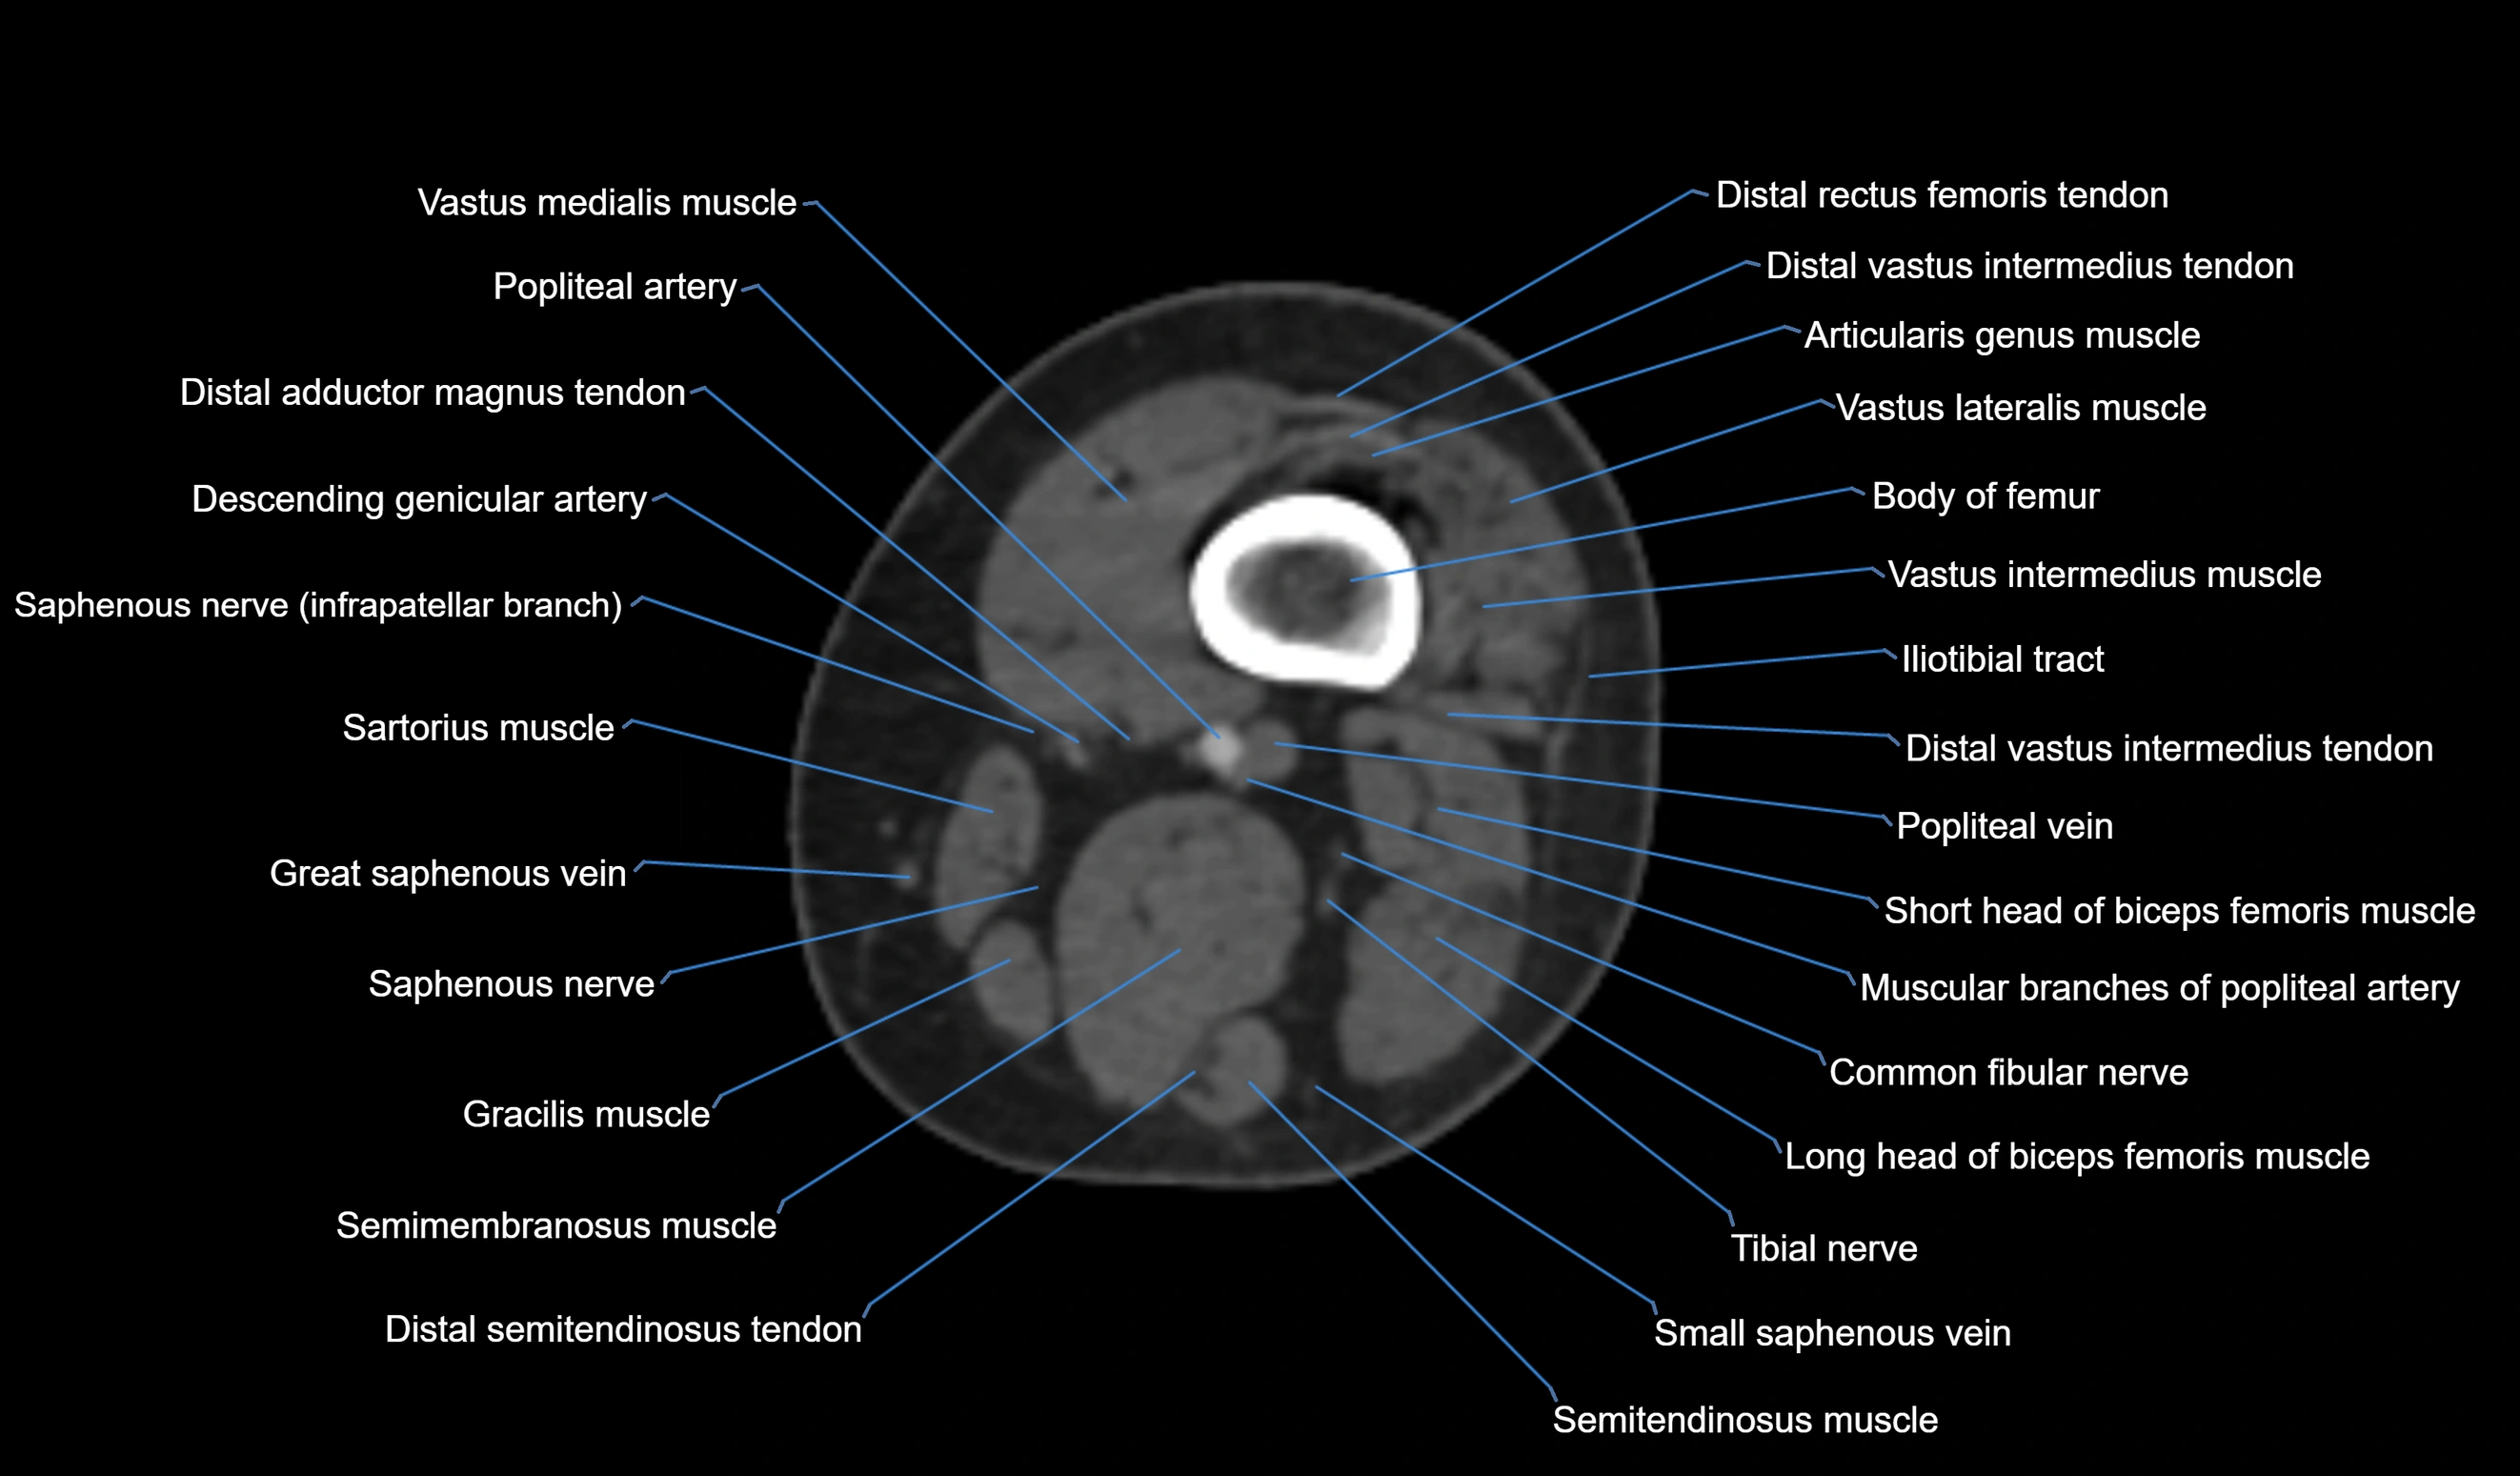

- Body of femur

- Distal adductor magnus tendon

- Distal rectus femoris tendon

- Distal vastus intermedius tendon

- Distal vastus lateralis tendon

- Popliteal artery

- Popliteal vein

- Sartorius muscle

- Semimembranosus muscle

- Semitendinosus muscle

- Small saphenous vein

- Tibial nerve

- Vastus lateralis muscle

- Vastus medialis muscle